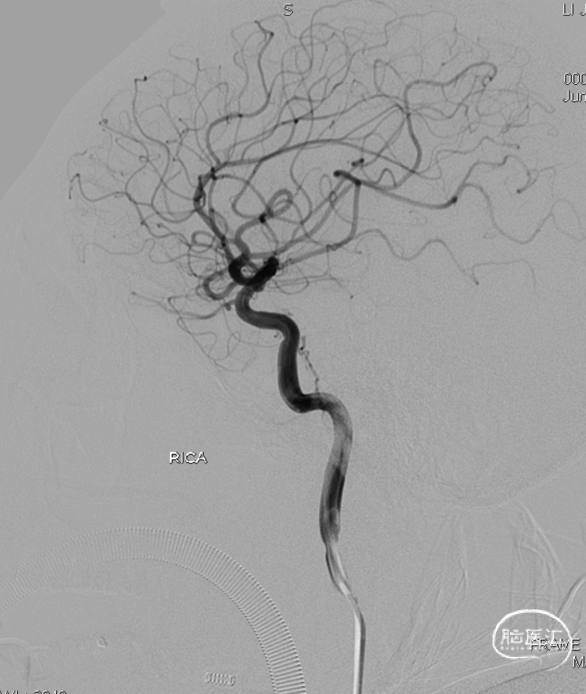

术前CT见左侧眼上静脉扩张

左侧咽升供血的HCDAVF,逆流至海绵窦,经眼上静脉-面静脉引流。

Echelon微导管超选面静脉,后通过眼上静脉超选至海绵窦,进一步超选至瘘口,微导管造影确认在位。

术后造影见瘘口不显影。